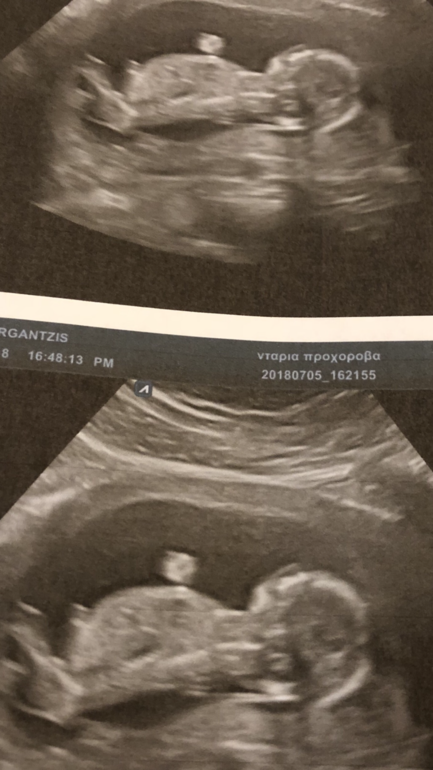

Идёт 14я неделька, я уже вернулась из Москвы в Грецию и нашла замечательного доктора, который будет и роды принимать! Сегодня сходила к нему с мужем , рассказала про все лекарства, которые принимаю после удачного ЭКО. Он был в шоке от их количества)))) Гематолог назначила вессел дуэ ф из-за склонности к тромбофилии, но он сказал вернуться к клексану т к если кровотечение на весселе вдруг случится - его фиг остановишь ведь вессел гепарин длительного действия в отличие от клексана... самое главное - с малышом все хорошо! Растём потиХоньку:) доктор думает, что пацан растёт :) а вы как считаете?